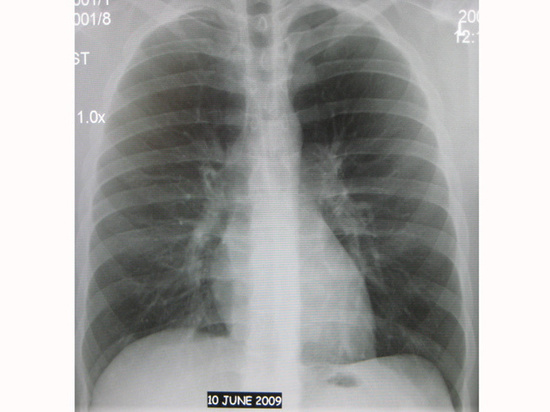

Курение